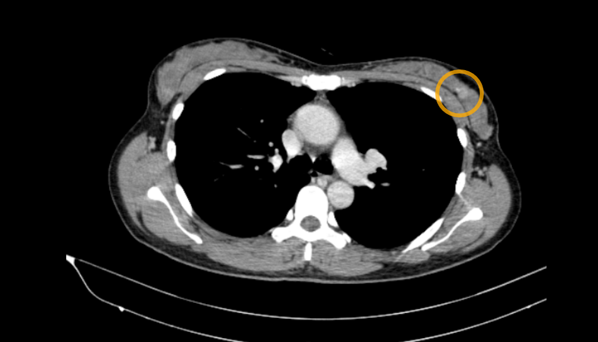

- Chụp XQuang tuyến vú: Vài nốt vi vôi hóa trung tâm rải rác hai vú - BIRADs 2.  ¼ trên ngoài vú phải có đám tăng đậm độ bất đối xứng kích thước 30x33mm - BIRADs 3.

Hình 1. Vài nốt vi vôi hóa rải rác (mũi tên vàng). Đám tăng đậm độ bất đối xứng ở vú phải (mũi tên xanh)